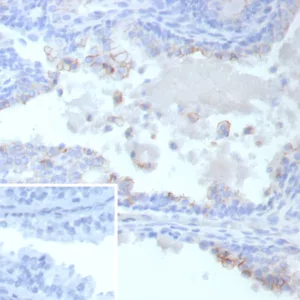

Immunohistochemistry is a technique used to detect and visualize specific proteins or antigens within tissue sections, typically from formalin-fixed, paraffin-embedded (FFPE) samples. Immunohistochemistry provides valuable information about localization, differential expression, tissue morphology, and disease pathogenesis. IHC provides quantitative data for validating the presence of a specific protein of interest in tissue samples and antibodies. Overall, IHC is valuable for understanding protein localization, tissue structure, and disease pathology. It is widely used in research and clinical diagnostics for various applications, including cancer diagnosis, neuroscience, and developmental biology.

Immunohistochemistry